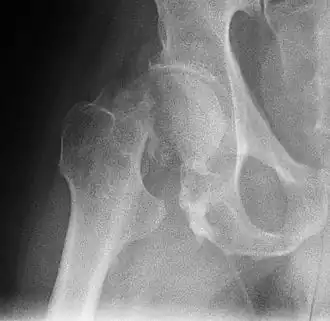

![]() Шейка бедра - типичная локализация патологического перелома | |

Типичная локализация патологических переломов — шейка бедренной кости, позвонки, дистальный эпифиз лучевой кости (перелом Коллиса). После исключения иных причин патологического перелома (неопластический процесс и др.) пациенту ставится диагноз «остеопороз», вне зависимости от данных денситометрии костей.